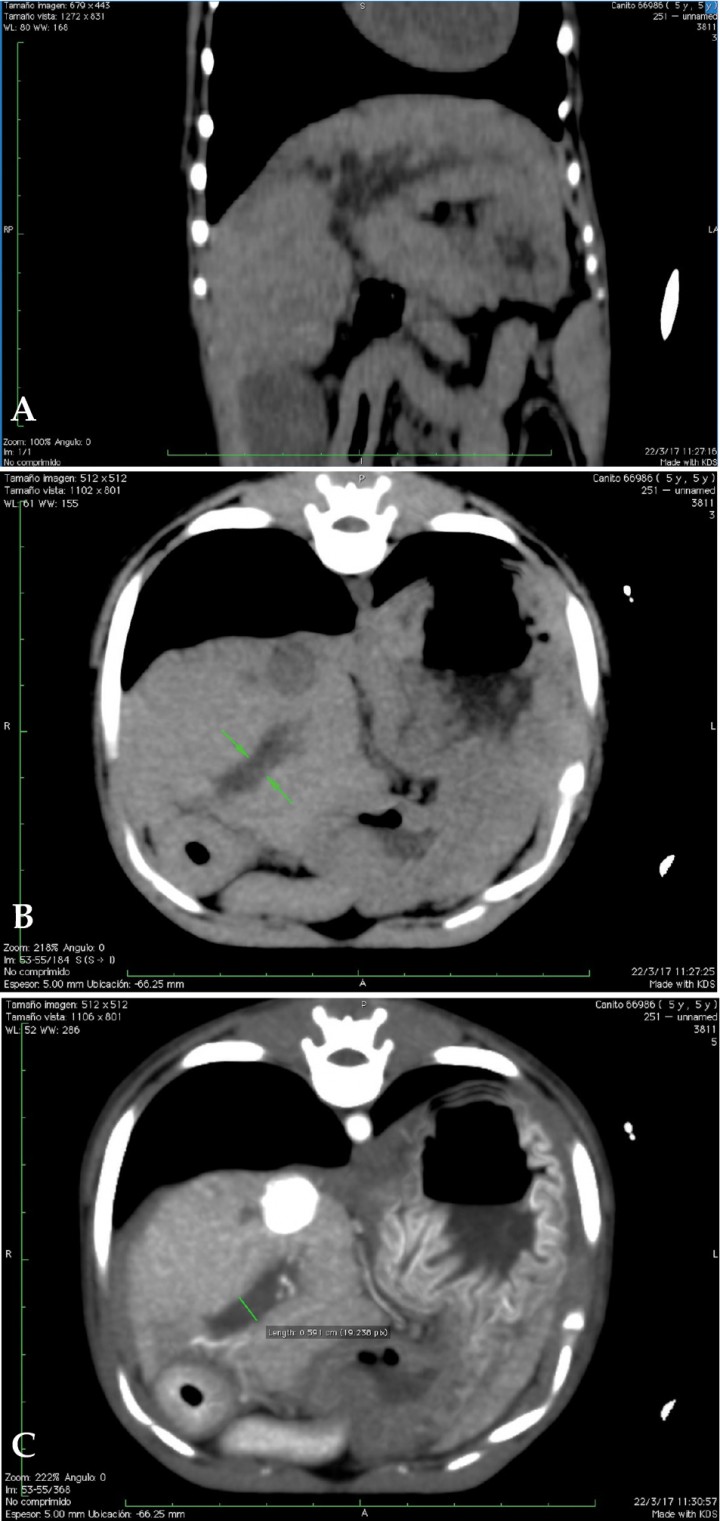

Para descarte de posible obstrucción del tracto biliar extrahepático se procedió a estudio mediante TC (Figs. 8 y 9). No se observó ninguna causa que pudiera justificar la dilatación de la vía biliar.

<p>(A) Reconstrucción multiplanar (MPR) en plano dorsal en ventana de tejido blando. Imagen sin contraste. Se identifican, hipodensos, los conductos biliares dilatados. (B y C) Imágenes axiales pre y postcontraste del conducto biliar común distendido, sin evidencias de obstrucción mecánica del mismo.</p>

Figura 8

(A) Reconstrucción multiplanar (MPR) en plano dorsal en ventana de tejido blando. Imagen sin contraste. Se identifican, hipodensos, los conductos biliares dilatados. (B y C) Imágenes axiales pre y postcontraste del conducto biliar común distendido, sin evidencias de obstrucción mecánica del mismo.

<p>Imágenes axiales con contraste a nivel renal. (A) Dilatación de la vena cava con múltiples vasos sanguíneos tortuosos adyacentes (shunts portosistémicos adquiridos), urolito en pelvis del riñón derecho. Áreas estriadas hipodensas (captación de contraste irregular) en ambas corticales renales. (B) Dilatación de la vena renal izquierda y pequeños vasos sanguíneos de aspecto tortuosos en la proximidad del riñón izquierdo (shunts portosistémicos adquiridos). Urolito en pelvis del riñón izquierdo. </p>

Figura 9

Imágenes axiales con contraste a nivel renal. (A) Dilatación de la vena cava con múltiples vasos sanguíneos tortuosos adyacentes (shunts portosistémicos adquiridos), urolito en pelvis del riñón derecho. Áreas estriadas hipodensas (captación de contraste irregular) en ambas corticales renales. (B) Dilatación de la vena renal izquierda y pequeños vasos sanguíneos de aspecto tortuosos en la proximidad del riñón izquierdo (shunts portosistémicos adquiridos). Urolito en pelvis del riñón izquierdo.